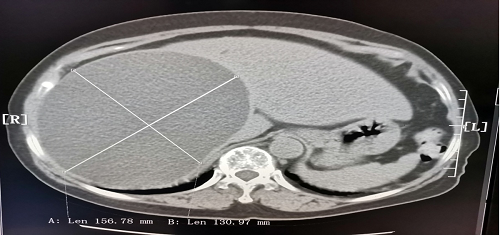

今日房县网讯 11月28日上午,房县人民医院急诊科主任雷禹接诊的一位80岁高龄女性患者,其CT图像显示肝脏上长一14cmx15cm巨大囊肿. 且紧贴肝脏表面,有随时破裂,引起大出血的风险,紧张的术前检查中发现患者患有高血压、血尿(+++)、白细胞增高等异常情况,需要进一步治疗才具备手术条件,但不及时手术,又存在囊肿随时破裂危及患者生命的巨大风险。